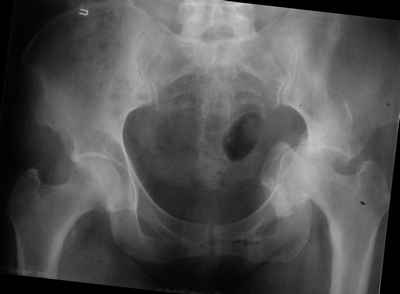

Уважаемые коллеги, возник вопрос по лечению нашей пациентки 60 лет. Около года назад множественная травма: в том числе Т-образный перелом вертлужной впадины. На сегодняшний день сращение отломков имеется на ограниченных участках, имеется дефект задней колонны вертлужной впадины. Движения неплохие, ходит с костылями, приступая на ногу. По мнению эдопротезистов при установке антипротрузионного кольца или октопуса не хватит костного материала и необходимо перед протезированием выполнить реконструкцию впадины, иначе чашка протеза неминуемо выпадет.Просьбы поделиться положительным и отрицательным опытом протезирования в подобных случаях.Возможно ли обойтись без реконструкции?Или лучше с ней?С уважением РАВ.